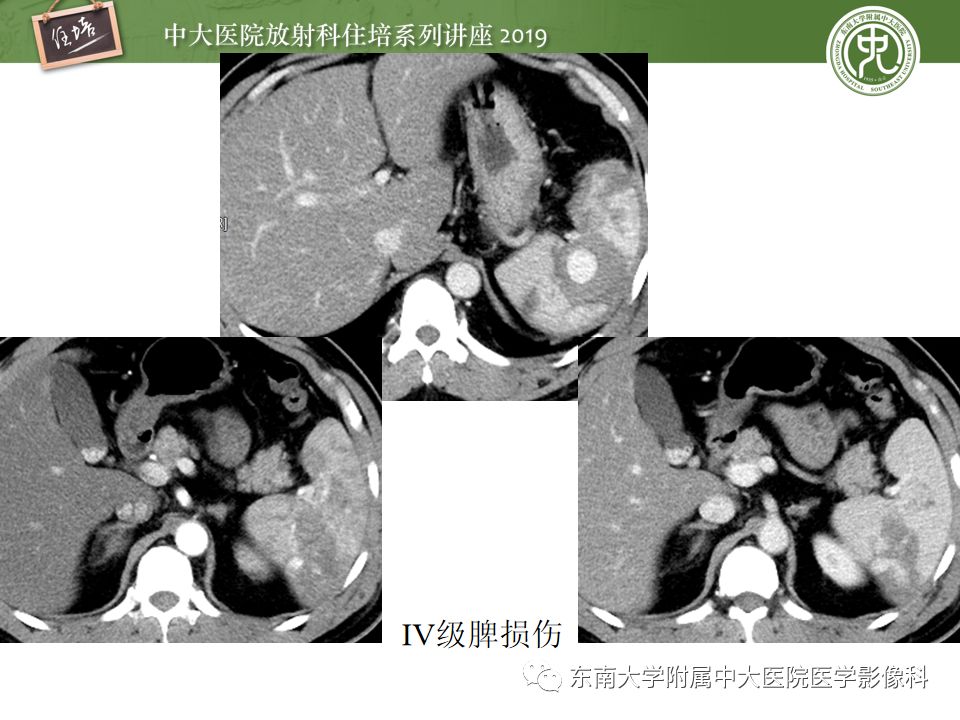

腹腔实性脏器钝性外伤影像诊断